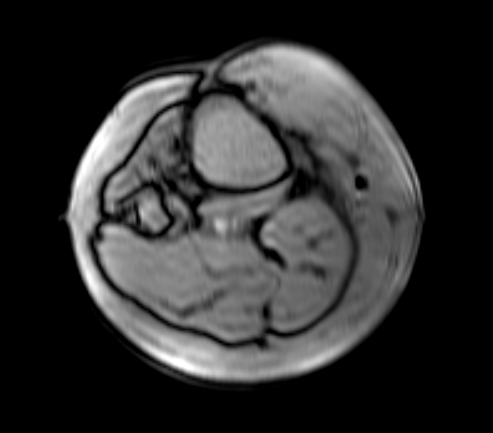

Az eRAD PACS támogatja az ablak szélességének és közepének előzetes beállításait. Az előzetes beállítások lehetővé teszik egy vagy több beállítás csoportosítását egy specifikus funkcióra. Ezután ezek a beállítások használhatók, ha kiválasztja őket a listából. Előre beállított ablak és szint esetén létrehozhat modalitás-specifikus ablak-/szintpárokat, és alkalmazhatja azokat a jelenlegi képhez úgy, hogy kiválasztja a címkét a listából. Az ablakok és szintértékek előre beállított listája nyilvántartja az összes mentett ablakolási beállítást egy specifikus modalitás típushoz. Az előre beállított ablakolási lista az Ablakolás eszköztárban jelenik meg. Az előre beállított értékek listája a legördíthető menüben található. Néhány alapértelmezett érték megtalálható az alapértelmezett ablakolási listában.

Néha a továbbított képek nem megfelelően beállított ablakszélességgel és központi értékekkel rendelkeznek, vagy a technikus hibás értékeket csatolt a képobjektumokhoz. Az ilyen helyzetek kezeléséhez az eRAD PACS konfigurációs beállításokkal rendelkezik, amelyek lehetővé teszik az alapértelmezett beállítások felülírását.

Három beállítás létezik az ablakolási problémák megoldására: